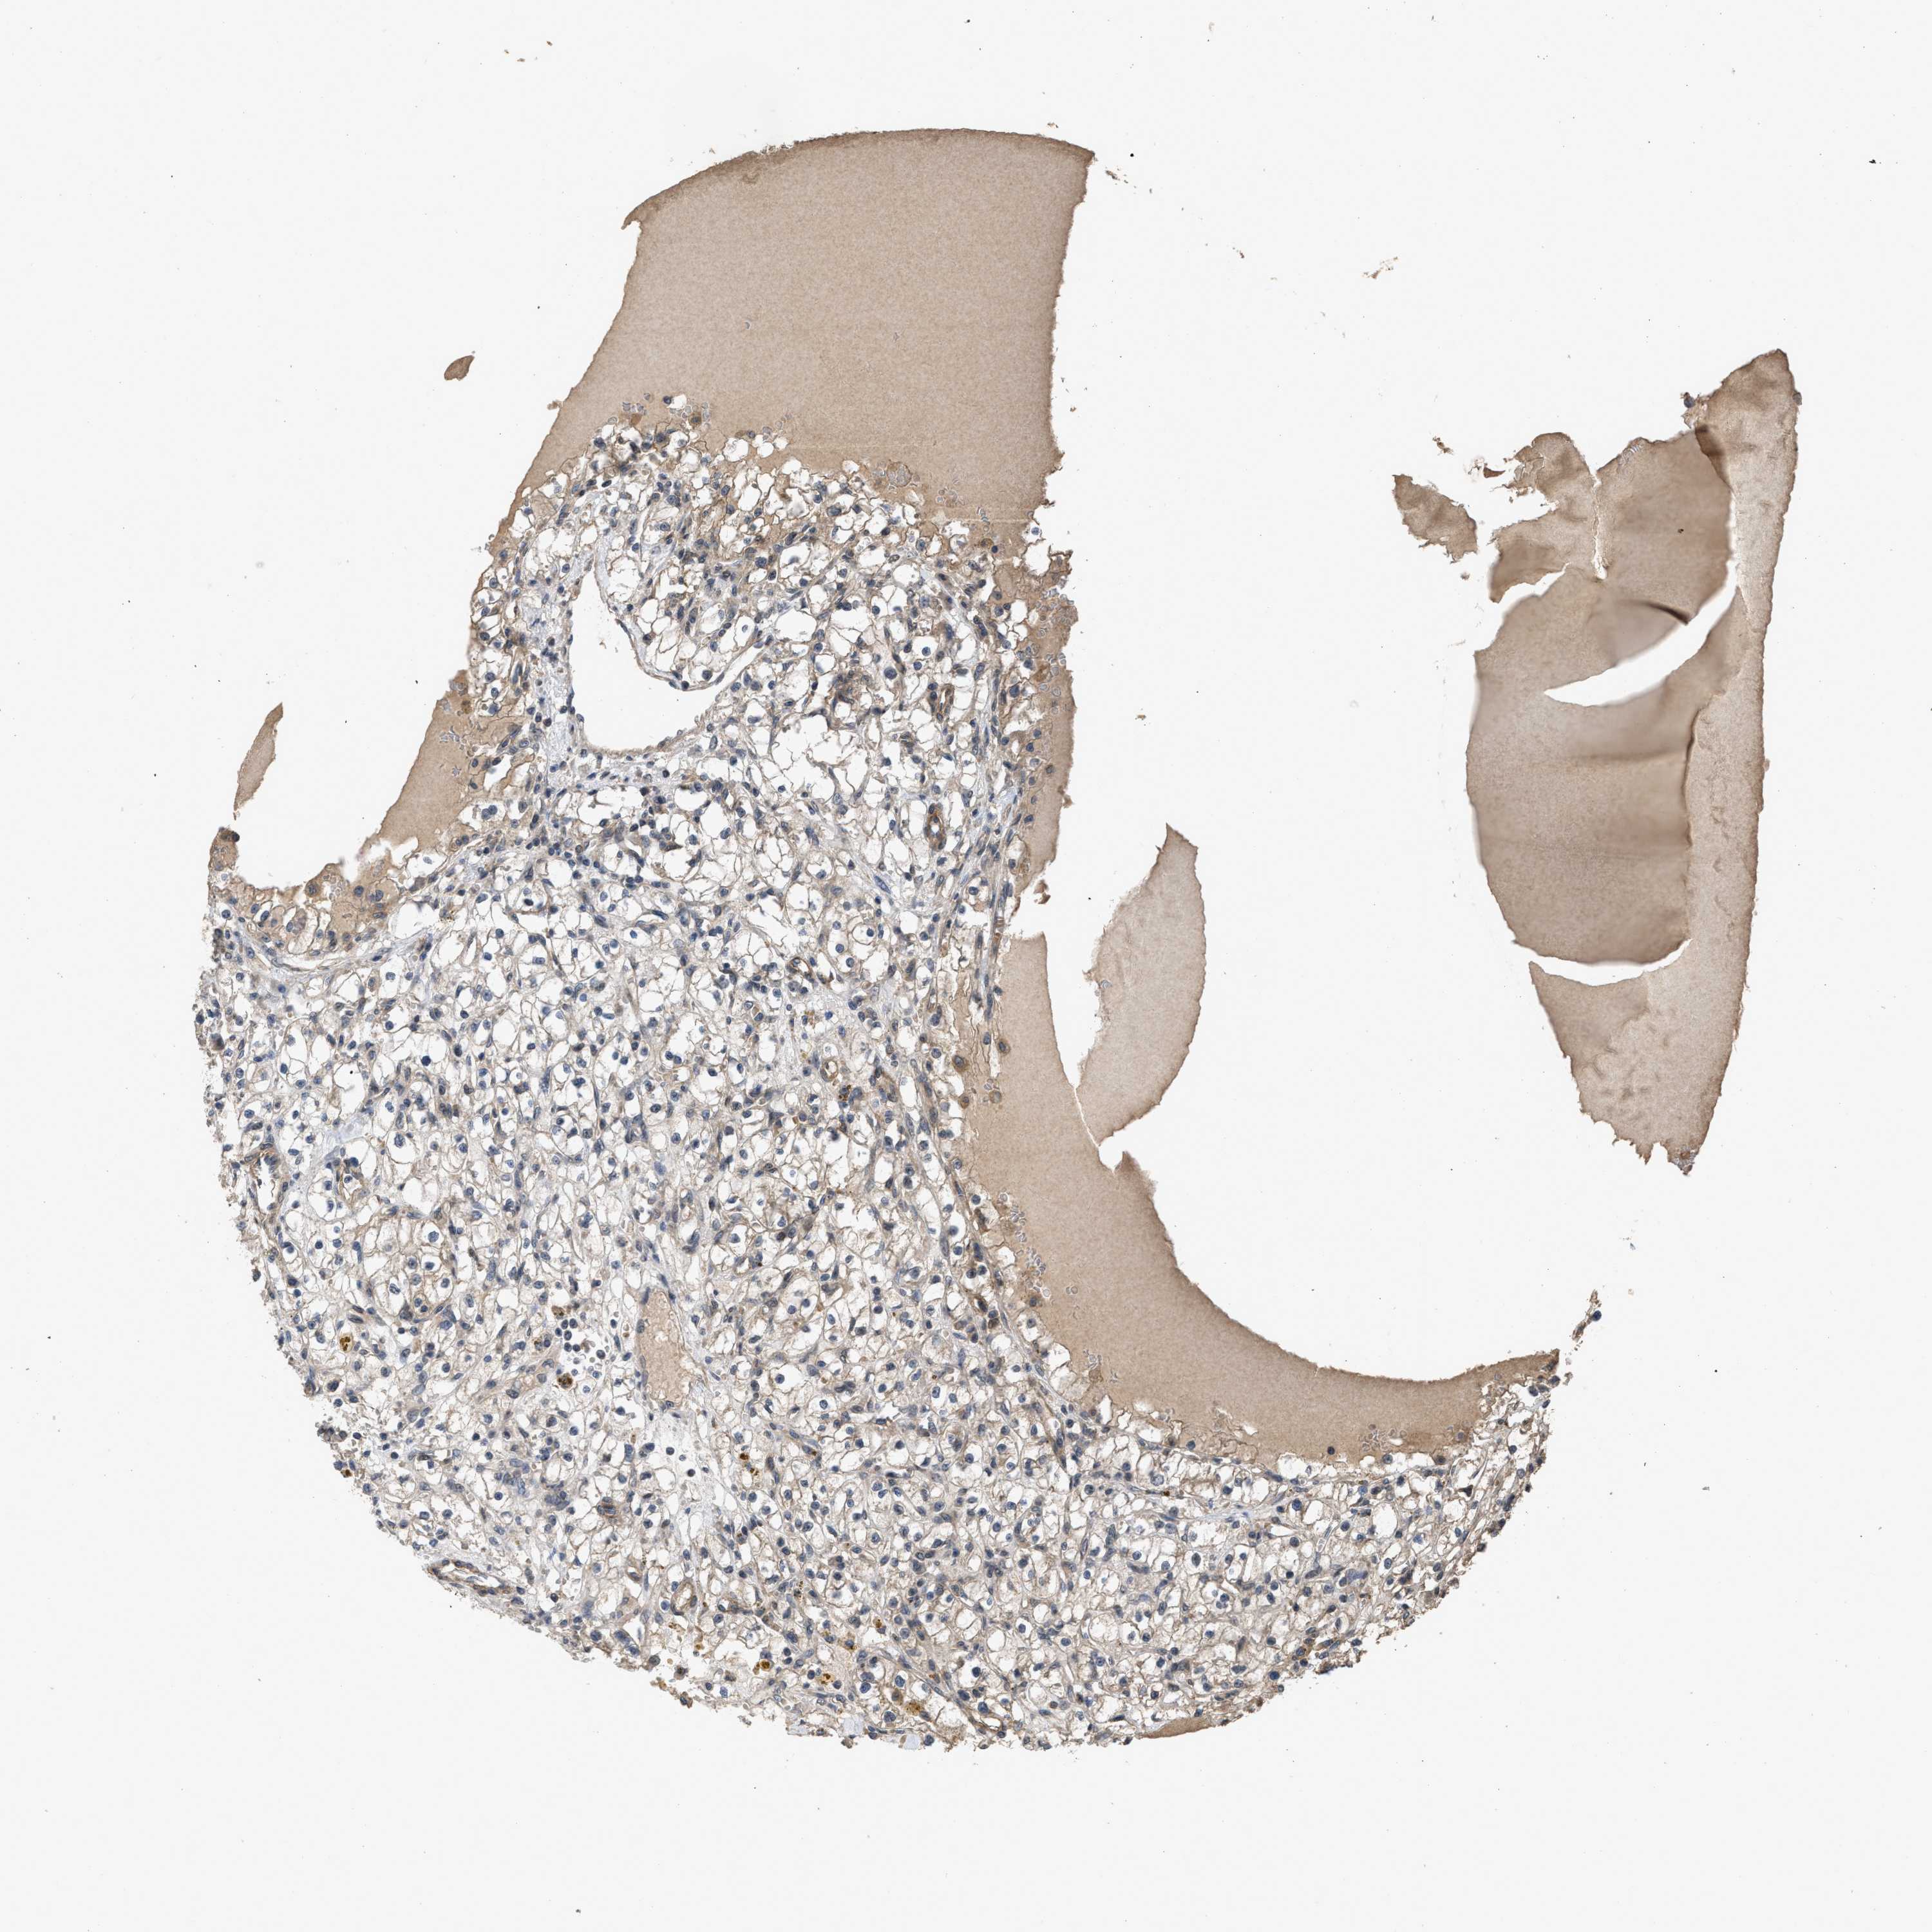

KIDNEY RENAL CLEAR CELL CARCINOMA (VALIDATION) - Interactive survival scatter ploti

The Survival Scatter plot shows the clinical status (i.e. dead or alive) for all individuals in the patient cohort, based on the same data that underlies the corresponding Kaplan-Meier plots. Patients that are alive at last time for follow-up are shown in blue and patients who have died during the study are shown in red.

The x-axis shows the expression levels (FPKM) of the investigated gene in the tumor tissue at the time of diagnosis. The y-axis shows the follow-up time after diagnosis (years). Both axes are complimented with kernel density curves demonstrating the data density over the axes. The top density plot shows the expression levels (FPKM) distribution among dead (red) and alive patients (blue). The right density plot shows the data density of the survived years of dead patients with high and low expression levels respectively, stratified using the cutoff indicated by the vertical dashed line through the Survival Scatter plot. This cutoff is automatically defined based on the FPKM cutoff that minimizes the p-score. The cutoff can be changed by dragging the vertical line or by entering a cutoff value in the square labeled "Current cut-off".

Under the Survival Scatter plot the p-score landscape (black curve; left axis) is shown together with dead median separation (red curve; right axis). Dead median separation is the difference in median mRNA expression between patients who have died with high and low expression, respectively. It is calculated as follows: median FPKM expression of dead patients with high expression - median FPKM expression of dead patients with low expression. This is intended to aid the user in visually exploring custom cutoffs and the associated p-scores and dead median separation.

Individual patient data is displayed and can be filtered by clicking on one or more of the category buttons on the top of the page. Categories describing expression level and patient information include: high, low, alive, dead, female, male and tumor stages. The scale of the x-axis can be toggled between linear and log-scale by clicking on the "x log" button. Mouse-over function shows TCGA ID, patient information and mRNA expression (FPKM) for each patient.

& Survival analysisi

Kaplan-Meier plots summarize results from analysis of correlation between mRNA expression level and patient survival. Patients were divided based on level of expression into one of the two groups "low" (under cut off) or "high" (over cut off). X-axis shows time for survival (years) and y-axis shows the probability of survival, where 1.0 corresponds to 100 percent.

UTRN is validated prognostic, high expression is favorable in Kidney Renal Clear Cell Carcinoma (validation)

Best expression cut offi

Based on the FPKM value of each gene, patients were classified into two groups and association between prognosis (survival) and gene expression (FPKM) was examined. The best expression cut-off refers the FPKM value that yields maximal difference with regard to survival between the two groups at the lowest log-rank P-value. Best expression cut-off was selected based on survival analysis .

When clicking on this number, the vertical dashed line indicating cut-off, the interactive survival plot, and the Kaplan-Meier curve will be adjusted to show results based on the best expression cut-off.

: 47.69

Median expressioni

Median expression refers to the median FPKM value calculated based on the gene expression (FPKM) data from all patients in this dataset. When clicking on this number, the vertical dashed line indicating cut-off, the interactive survival plot, and the Kaplan-Meier curve will be adjusted to show results based on the median expression.

: N/A

Median follow up timei

Median follow up time refers to the median time (years) after diagnosis with this type of cancer, based on clinical data from all patients in this dataset.

P scorei

Log-rank P value for Kaplan-Meier plot showing results from analysis of correlation between mRNA expression level and patient survival.

N/A

5-year survival highi

5-year survival for patients with higher expression than the expression cutoff.

For melanoma and glioma, 3-year survival is shown.

5-year survival lowi

5-year survival for patients with lower expression than the expression cutoff.

Average pTPM 53.2

Number of samples 100